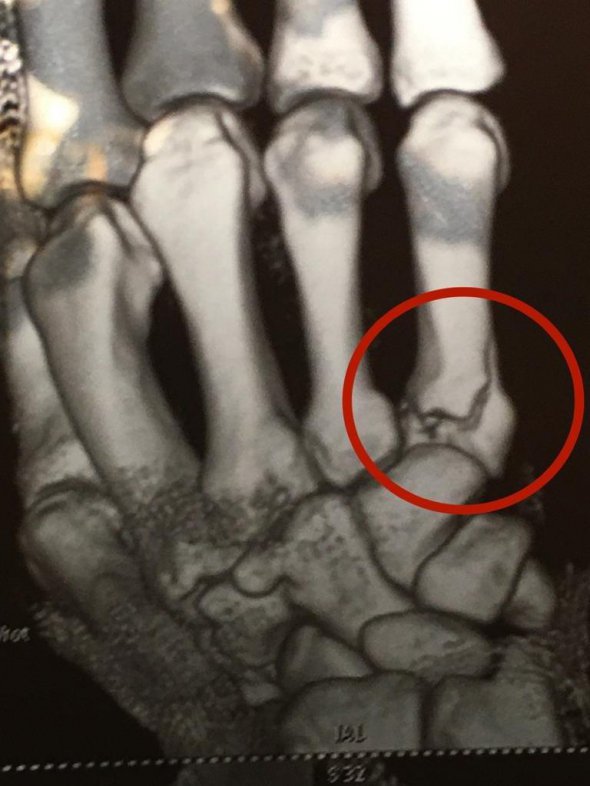

"Після бою лікар турніру Юрій Дехтярьов надав нашому чемпіону невідкладну допомогу. На жаль, рентгенологічне обстеження підтвердило осколковий перелом п'ятої п'ясткової кістки в області суглоба. Зазначу, що Артема консультували троє провідних українських травматологів. Зараз перед медичною службою команди стоїть одне завдання: у мінімально короткий термін відновити функцію розбитого суглоба і провести кваліфіковану реабілітацію. За термінами на це піде не менше 2 місяців", - сказав Попов у коментарі "Чемпіону".